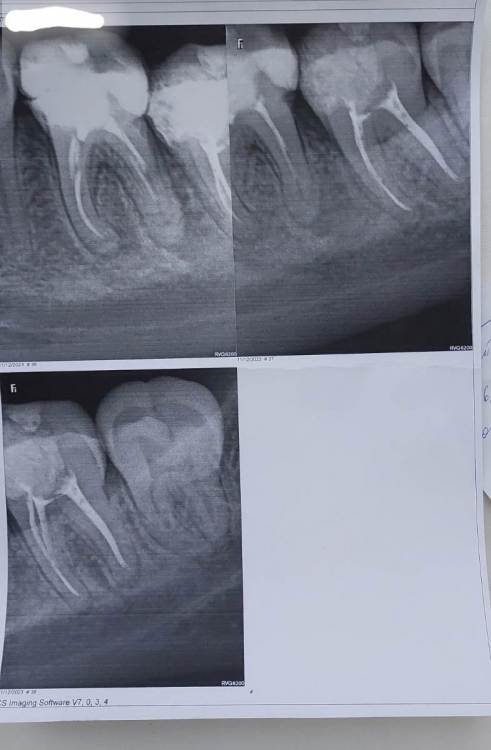

tARTu Опубликовано 11 декабря, 2023 Поделиться Опубликовано 11 декабря, 2023 Добрый день! На фоне ОРВИ, температуры 39 и после вечерней ингаляции на утро возник флюс. Сделали разрез, поставили дренаж, назначили антибиотики и содовые ванночки. Через два дня сделала снимок (наверху слева - 36 зуб, пролечен лет 7 назад; наверху справа 37 - пролечен пару месяцев назад; внизу 37 на стыке с 38). Дренаж убрали. Сказали пить еще дней 5 антибиотики, продолжать полоскать. Если будет рецидив периостита, 36 удалить. Хотелось бы послушать мнение специалистов на этот счёт. Спасибо! Ссылка на комментарий

Notherbrick Опубликовано 11 декабря, 2023 Поделиться Опубликовано 11 декабря, 2023 Здравствуйте. Скорее всего речь шла об обострении периодонтита. Прогноз у 36 зуба неблагоприятный. Ссылка на комментарий

tARTu Опубликовано 11 декабря, 2023 Автор Поделиться Опубликовано 11 декабря, 2023 2 часа назад, Notherbrick сказал: Здравствуйте. Скорее всего речь шла об обострении периодонтита. Прогноз у 36 зуба неблагоприятный. Поняла, спасибо. 36 и не предлагают лечить, сразу удалять, если возникнут жалобы. Ссылка на комментарий